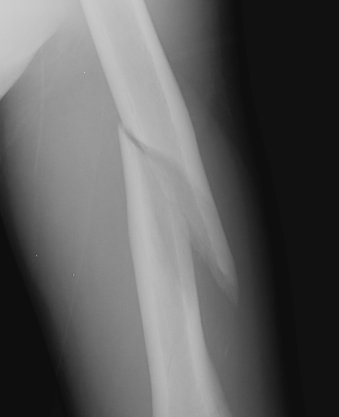

Return to Pathologic Fracture (Humerus)